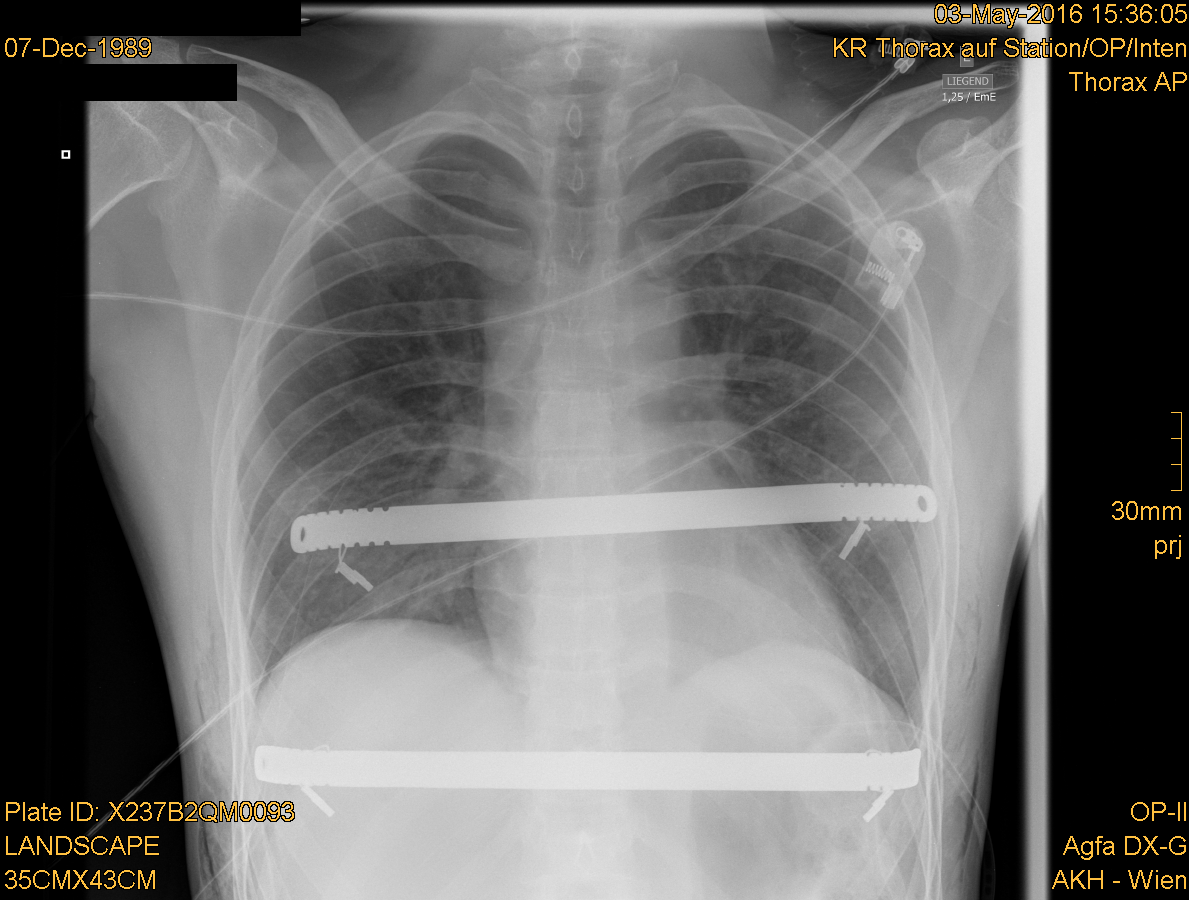

경미한 오목가슴은 교정이 필요하지 않다.[20] 심한 경우에는 침습적 시술이나 비침습적 시술, 또는 두 가지 모두를 사용하여 치료할 수 있다. 수술 전에는 일반적으로 CT 스캔, 폐 기능 검사, 심장학 검사(청진, ECG 등)를 포함한 여러 검사를 시행한다.[21] CT 스캔 후에는 Haller 지수를 측정하는데, 이는 횡경(늑골 내부 수평 거리)과 전후경(척추와 흉골 사이 최단 거리)의 비율이다.[22] Haller 지수가 3.25보다 크면 심각한 것으로 간주되며, 정상 가슴은 2.5이다.[17][23][24] 심폐 기능 검사는 폐활량과 심장 잡음을 확인하는 데 사용된다.[25]오목가슴 교정을 위한 최선의 수술 방법에 대해서는 논란이 있어 왔다. 외과 의사는 각 개인의 특성에 맞는 수술 방법을 선택해야 한다.[43] 수술적 교정은 호흡 문제나 심장 잡음 같은 기능적 증상을 개선하며, 극심한 경우 영구적 손상이 없다면 효과를 볼 수 있다.[44] 오목가슴 수술은 심혈관 기능을 유의미하게 개선하는 것으로 나타났지만,[45] 폐 기능 개선 여부는 아직 결론이 나지 않았다.[46] 오늘날 가장 인기 있는 오목가슴 수술 기술 중 하나는 MIRPE 또는 너스(Nuss) 수술로 알려진 최소 침습 수술이다.[47]

1987년, 버지니아주 노퍽의 어린이 왕의 딸 병원의 도널드 너스는 오목가슴의 최초 최소 침습적 교정술(MIRPE)을 시행했으며[52], 1997년 학회에서 발표했다.[52][53][54] "너스 시술"로 널리 알려진 이 2단계 시술은 하나 이상의 오목한 강철 막대를 흉부 내, 흉골 아래에 삽입하는 과정이다.[55] 막대는 흉골을 바깥쪽으로 밀어 변형을 교정하도록 볼록한 위치로 뒤집는다. 막대는 약 2년 동안 신체 내에 유지되지만, 최근에는 최대 5년까지 유지하는 경우도 있다. 뼈가 제자리에 굳어지면 외래 수술을 통해 막대를 제거한다. 처음에는 10세 미만 어린이를 대상으로 설계되었지만, 10대 후반과 20대 환자에게도 너스 시술이 성공적으로 이루어지고 있다.[56]

일본에서는 누두흉 수술의 표준적인 술식으로 너스(Nuss) 수술법이 자리 잡았다. 늑골 아래에 티타늄 또는 스테인리스 스틸 재질의 바와 필요에 따라 안정장치를 2~3년 동안 삽입한 후 제거하여 흉골을 들어 올리는 방법이다. 장점으로는 흉골 융기술 변법에 비해 가슴 앞부분의 흉터가 작고 눈에 띄지 않으며, 뼈를 절개하지 않으므로 흉골 융기술 변법과 같은 뼈에서 오는 통증이 없다. 또한, "함몰 치료" 외에 "[https://www.med.kagawa-u.ac.jp/~keisei/routo/basic/thinchest/ 편평 흉곽]"도 해결한다. 단점으로는 흉골 융기술 변법에서는 하지 않는 옆구리 부분 절개(바 삽입을 위해)로 수술 후 며칠 동안 상처 부위에 통증이 따르며, 경막외 마취가 필요하다. 또한, 합병증 위험도 있는데, 가와사키 의과대학 및 니시노미야 와타나베 심장 뇌·혈관 센터 누두흉 치료 센터 연구에서 스테로이드가 효과적이었다고 발표되었다. 수술 후 바 제거까지 바 편위를 방지하기 위해 유도와 같은 운동 제한이 있다.